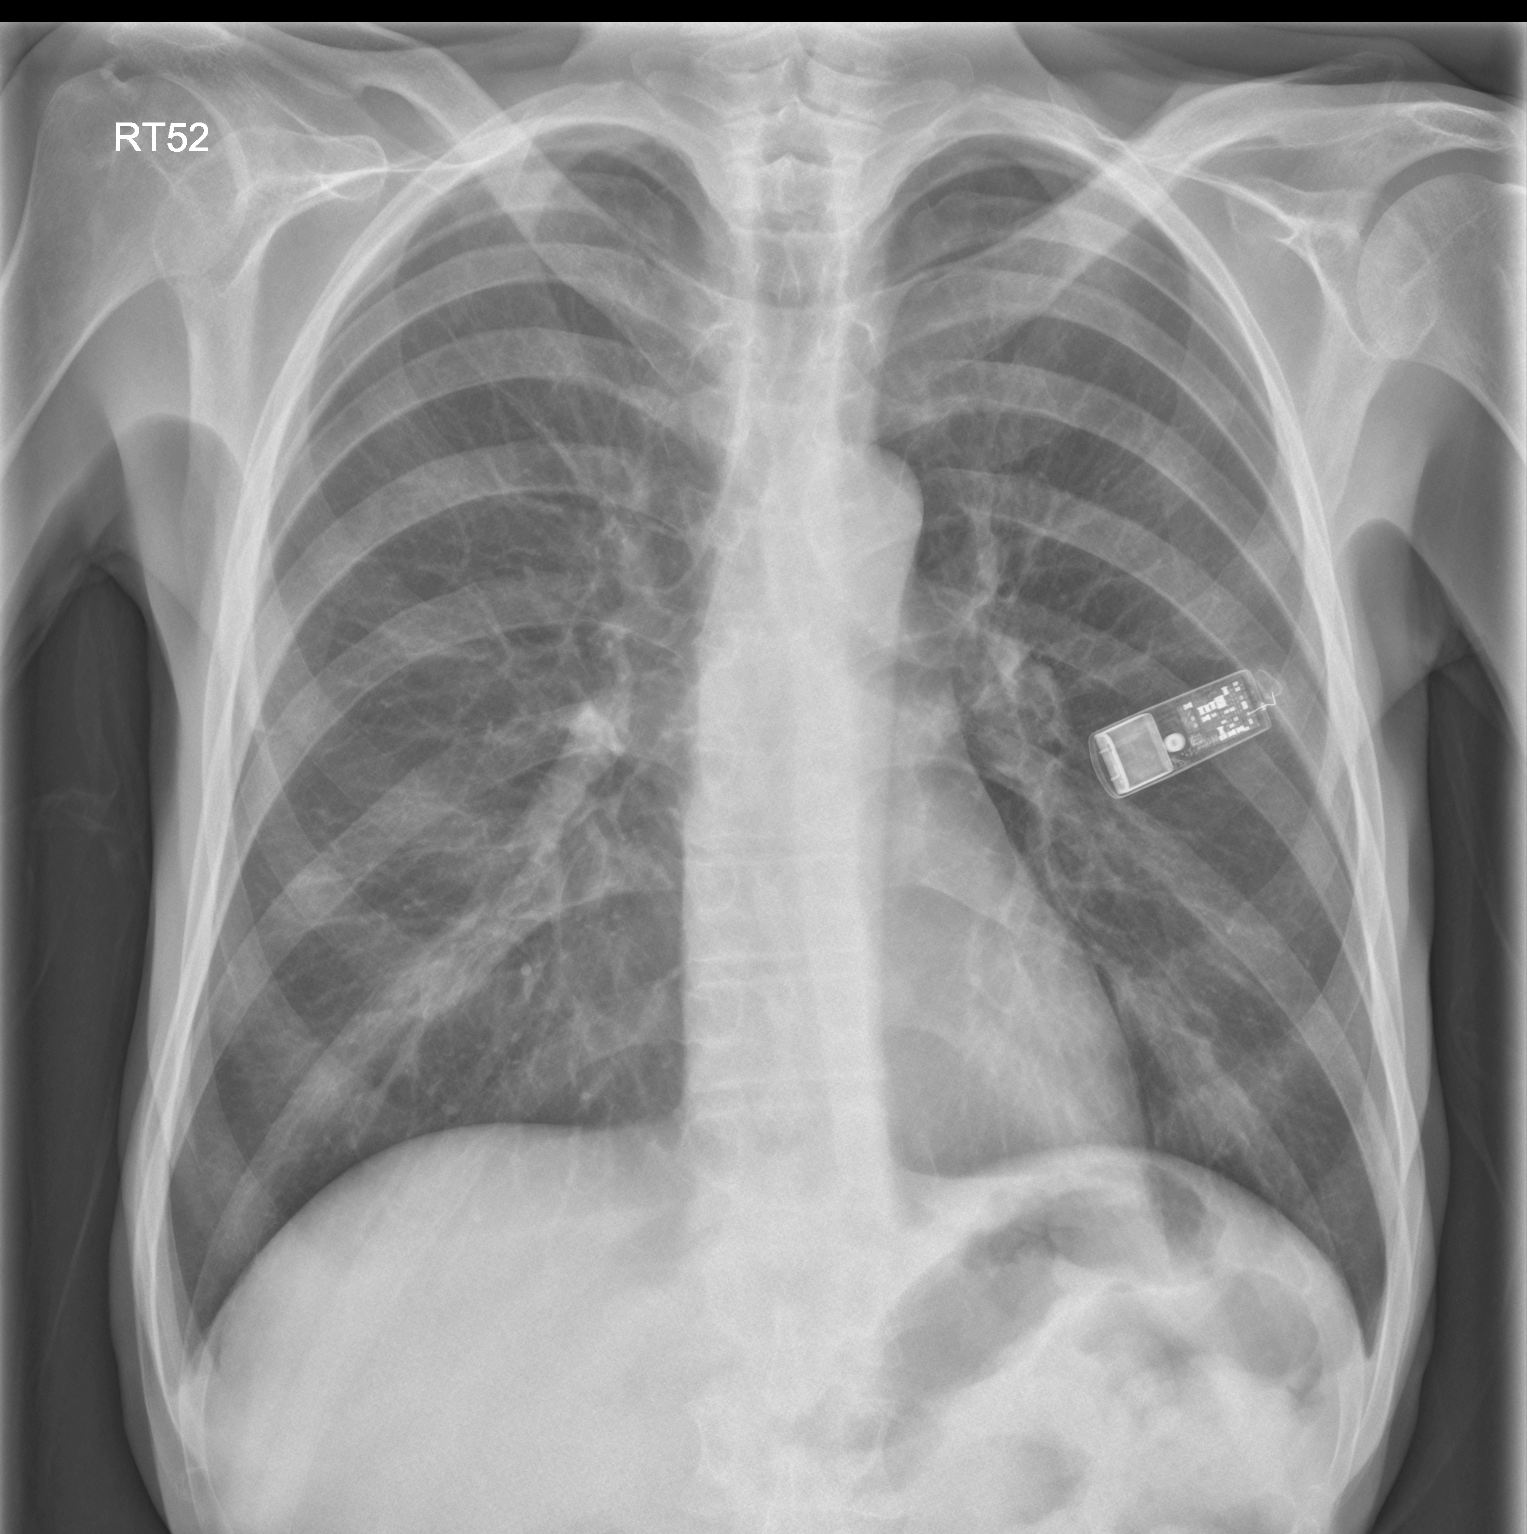

Implanted Cardiac Loop Recorder Loop Monitor X Ray implantable loop recorders, also known as insertable cardiac monitors, are small insertable devices that continuously monitor and. an implantable loop recorder (also known as an ilr) is a very small device which constantly monitors your heartbeat. It works much like a black box in an airplane, whereby. an implantable loop recorder is a device that records the. Loop Monitor X Ray.

Cardiac monitoring device, chest Xray Stock Image C040/3125 Loop Monitor X Ray almost all of the patients with implanted cardiac devices such as pacemakers, implantable cardioverter. implantable loop recorders, also known as insertable cardiac monitors, are small insertable devices that continuously monitor and. It works much like a black box in an airplane, whereby. the implantable loop recorder monitors the rate and rhythm of the heart. loop recorders. Loop Monitor X Ray.

Cardiac Loop Recorder XRay at Della Drummond blog Loop Monitor X Ray the implantable loop recorder monitors the rate and rhythm of the heart. loop recorders are implantable cardiac monitors to continuously record the cardiac rhythm in patients with. implantable loop recorders, also known as insertable cardiac monitors, are small insertable devices that continuously monitor and. an implantable loop recorder is a device that records the heartbeat continuously. Loop Monitor X Ray.

the xray doctor xrayoftheweek 43 that's not a USB stick...is it? Loop Monitor X Ray an implantable loop recorder (also known as an ilr) is a very small device which constantly monitors your heartbeat. implantable loop recorders, also known as insertable cardiac monitors, are small insertable devices that continuously monitor and. It works much like a black box in an airplane, whereby. an implantable loop recorder is a device that records the. Loop Monitor X Ray.